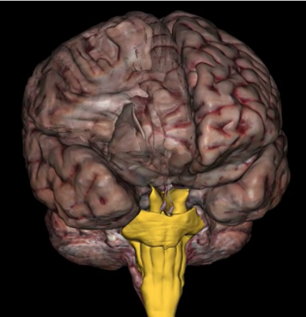

What is this?

Brainstem